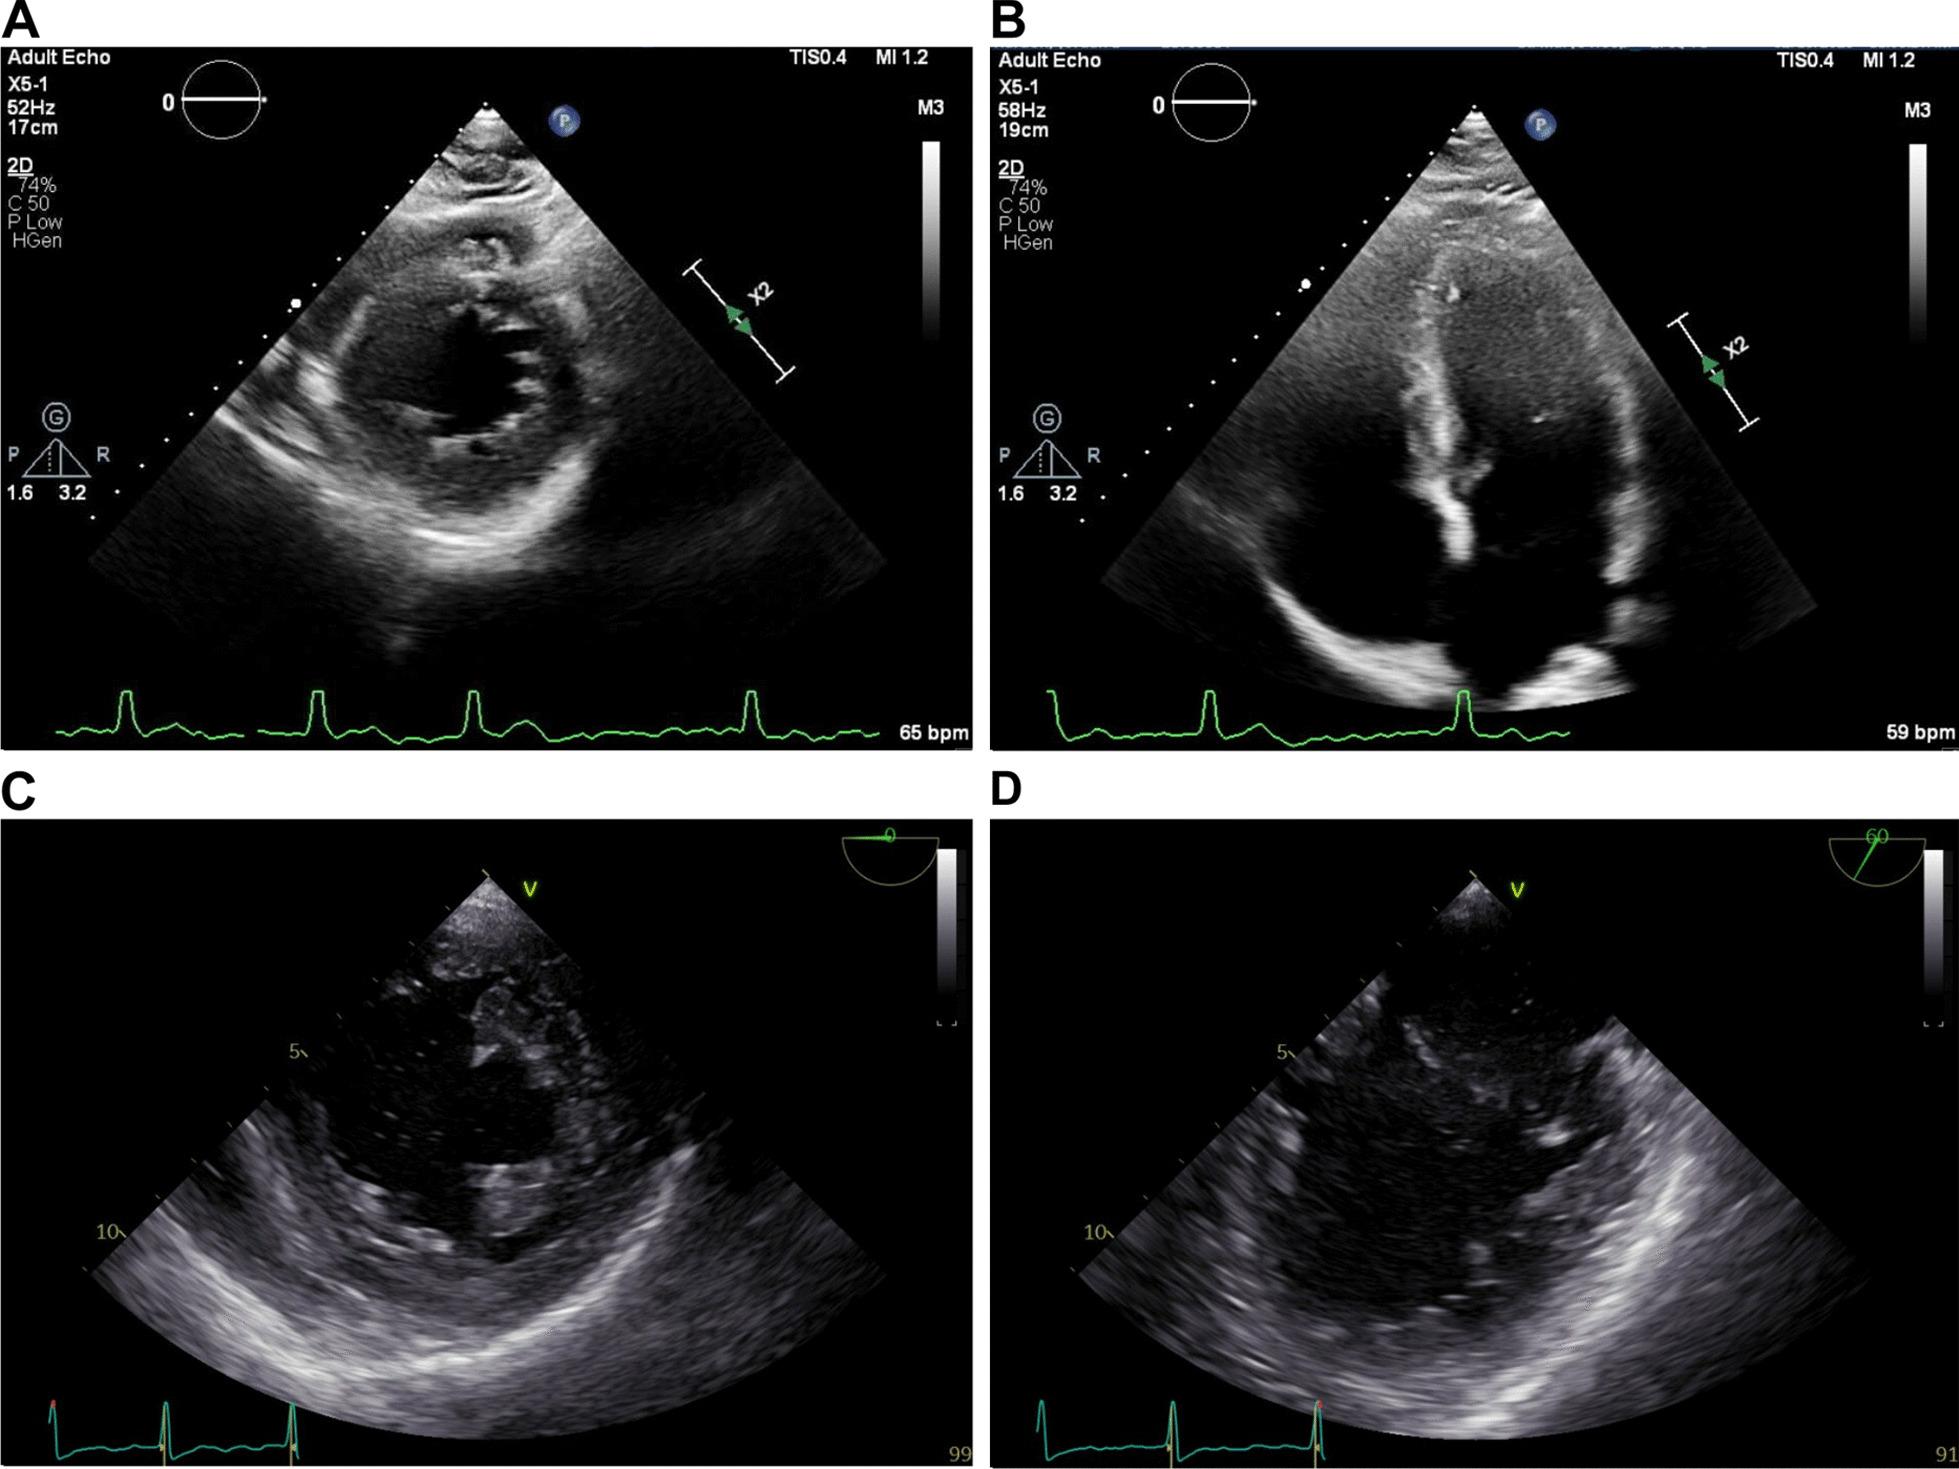

We describe a case of an African American male in his 20s that presented to our chronic pain clinic with lumbar radiculitis and developed atrial fibrillation 4 days after being started on gabapentin. Laboratory workup did not show significant abnormalities, including normal complete blood count, comprehensive metabolic panel, toxicology screen, and thyroid-stimulating hormone. Transthoracic and transesophageal echocardiography showed a patent foramen ovale with right-to-left shunt. The patient was initially treated with diltiazem for heart rate control and apixaban. Direct current cardioversion with successful conversion to sinus rhythm was performed 24 hours after admission. The patient was then discharged on apixaban and diltiazem. Apixaban was changed to low-dose aspirin 1 month after discharge.

我们描述了一位 20 多岁的非裔美国男性,因腰椎神经根炎到我们的慢性疼痛诊所就诊,在开始使用加巴喷丁后 4 天出现房颤。实验室检查无明显异常,包括正常的全血细胞计数、综合代谢小组、毒理学筛查和促甲状腺激素。经胸和经食管超声心动图显示卵圆孔未闭伴右向左分流。患者最初接受地尔硫卓控制心率和阿哌沙班治疗。入院 24 小时后进行直流电复律,成功转为窦性心律。随后患者出院,服用阿哌沙班和地尔硫卓。出院后 1 个月将阿哌沙班改为低剂量阿司匹林。